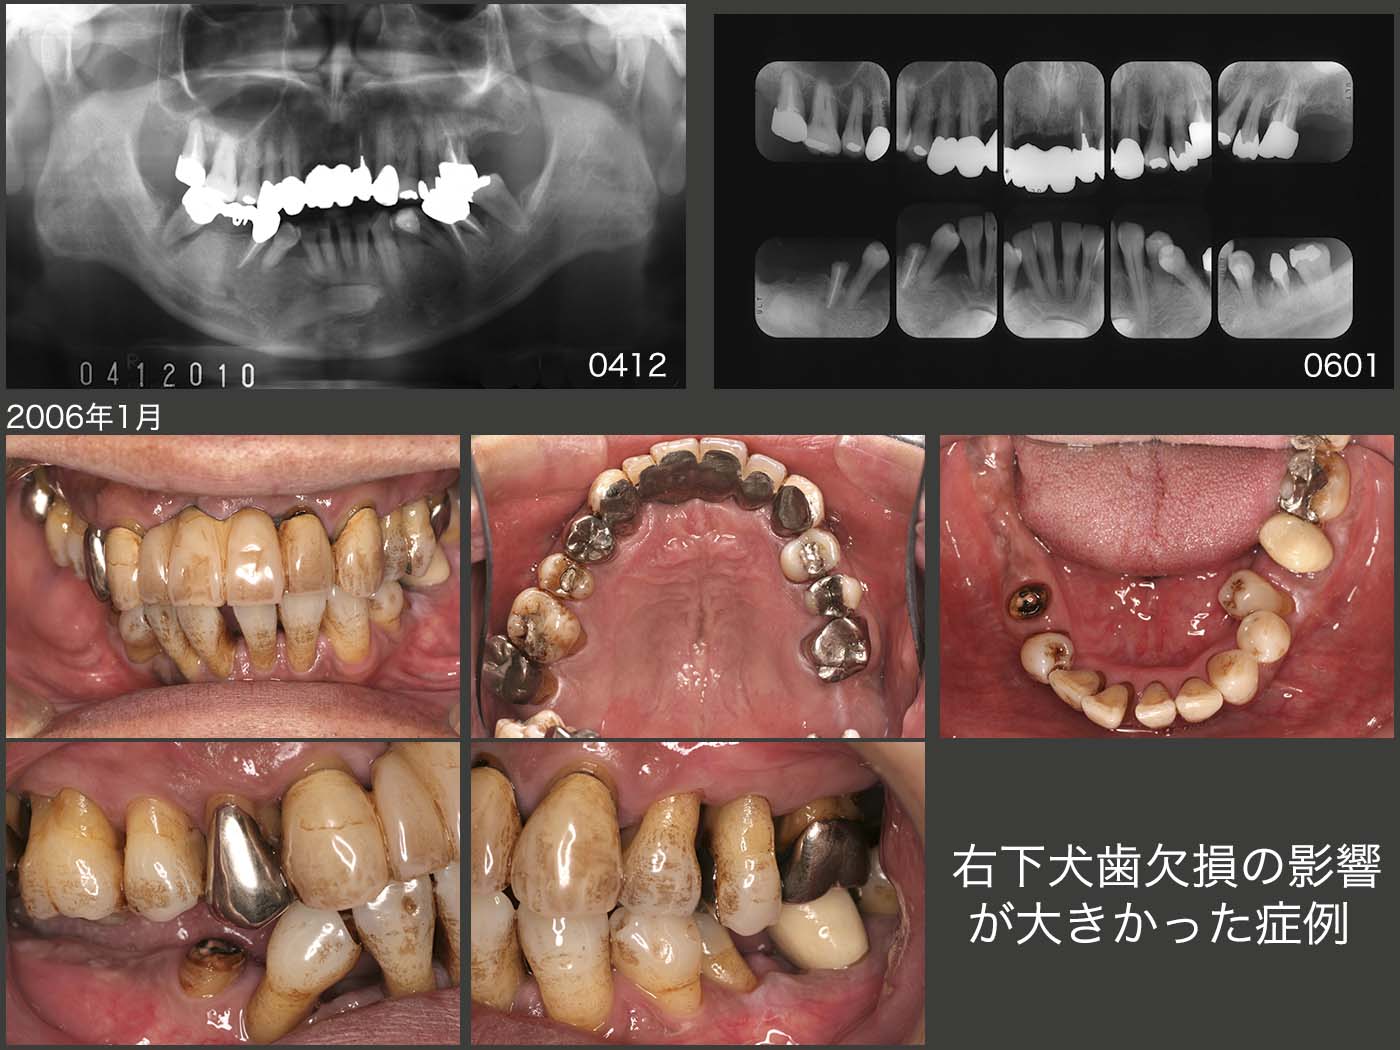

19.右下犬歯欠損の影響が大きかった症例

初診は2004年12月,56歳男性.右下ブリッジがグラグラするが主訴.保存不可能な右下7を抜去後,歯周基本治療を行い,一旦治療を終了した.

05年,左下6近心根に歯根破折が生じたため,ヘミセクションを行った.咬合支持歯が少なくなり,大分咀嚼しにくくなったため,やっと患者さんは本腰を入れて治療を受ける気になった.06年1月,術者も臼歯部咬合支持の獲得に向けて,治療を開始した.ここで,右下3が埋伏しており,機能していないことが気になった.

まず,近心傾斜している右下4および歯列から外れている左下5のアップライトを目指し,2006年5月,歯科矯正を開始し,10月終了した.これで,右下4の抜髄は避けることができた.しかし,右下⑤④3②のブリッジのみで,右側の咬合を全て担うのは難しいと考え,12月に右下6部にインプラントを1本植立した.但し,ブリッジとインプラントとを連結固定する必要まではないと考えた.